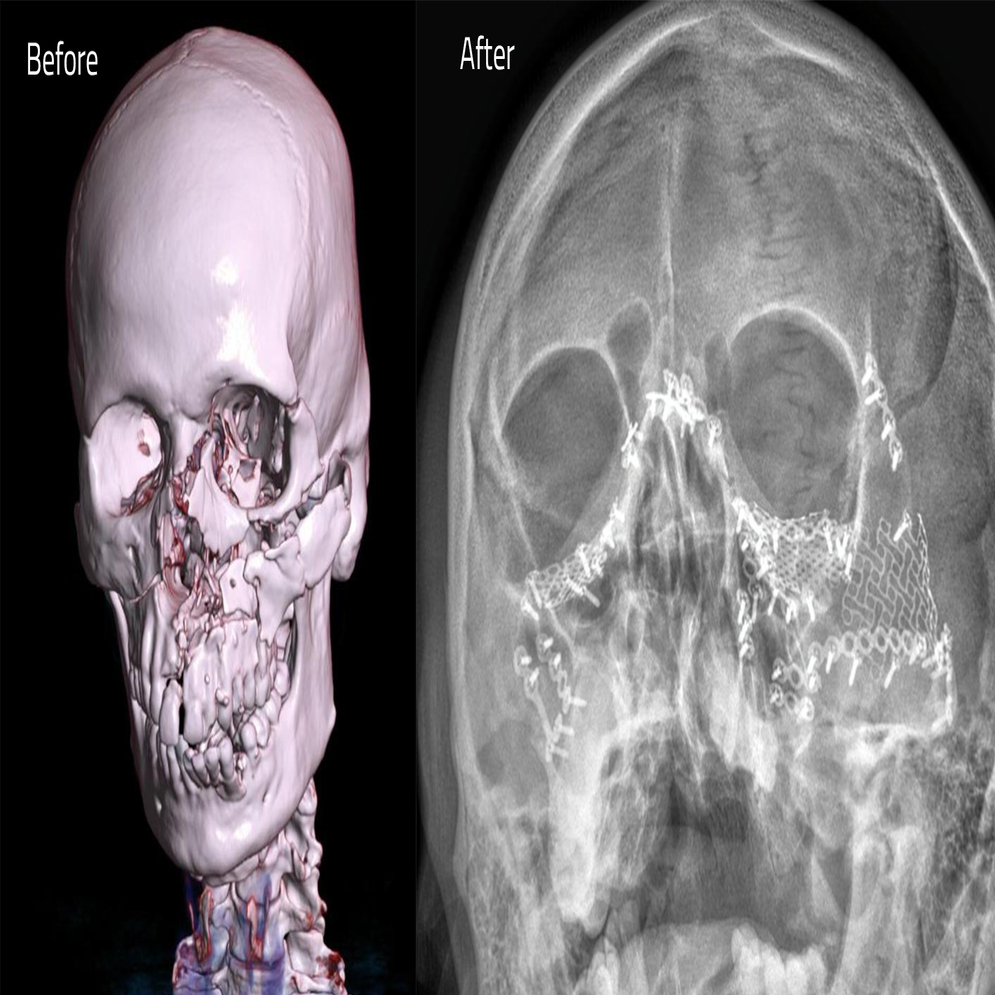

In this patient’s case, the injuries included multiple fractures of the jaw, cheekbones, nasal bones, and eye sockets, extensive loss of nasal cartilage and teeth, disruption of jaw alignment, and orbital injuries that posed a serious risk to vision. Due to the severity of the trauma, his nose was cut, his teeth were crushed, and his jaw was badly damaged, causing severe pain, heavy bleeding, and difficulty breathing.

The patient underwent a detailed surgical procedure called Open Reduction and Internal Fixation (ORIF) with multiple orbital reconstructions under general anesthesia. The surgery was led by Dr. Renju Prem, Lead Surgeon in Oral and Maxillofacial Surgery at Aster Hospital Mankhool, with anesthesia support from Dr. Abhishek J Narayan and Dr. Jawad Ebn Mohammed. The anesthesia team decided to opt for sub-mental intubation in view of extensive facial / nasal fractures. The team used multiple approaches to the maxillofacial skeleton starting from the mandible (“bottom to top approach”) to the cranial base. The external approaches were used carefully fix the broken bones, stabilize them with titanium plates and screws, rebuild the eye sockets, reposition the nerves, and restore the overall structure of the face. Damaged bone fragments and knocked-out teeth were removed, and the nasal structures were reconstructed to restore both function and appearance.